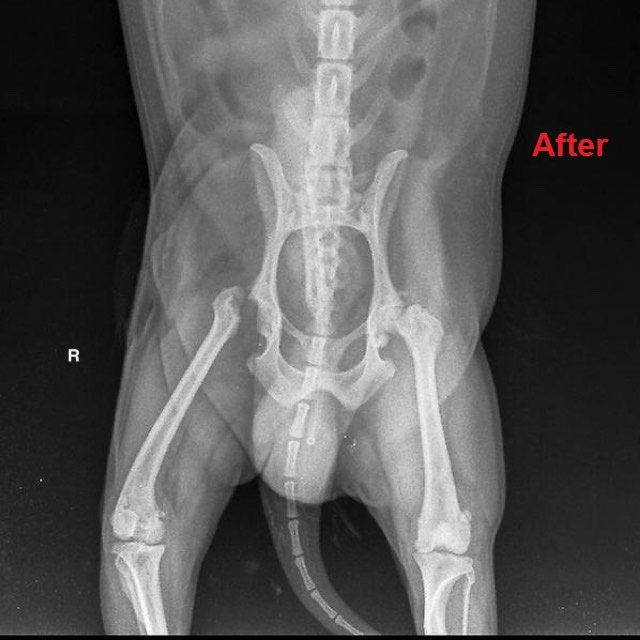

น้องโมจิได้รับการผ่าตัดโดยสัตวแพทย์ผู้เชี่ยวชาญด้านโรคกระดูกและข้อ โดยใช้เทคนิค Femeral head and neck excision หรือ FHNE ซึ่งเป็นการตัดเอาส่วนหัวและคอของกระดูกขาหลังส่วนต้นออกเพื่อลดการเสียดสีของหัวกระดูกกับเบ้ากระดูกเชิงกราน หลังจากนี้ร่างกายจะสร้างเนื้อเยื่อพังผืดเข้ามายึดเป็นข้อเทียมทดแทนส่วนที่ตัดออกไป การผ่าตัดเป็นไปได้ด้วยดี น้องโมจิฟื้นตัวไว และอยู่ดูแลภายหลังผ่าตัดที่โรงพยาบาลสัตว์ไอเว็ทจนตัดไหม ตอนนี้น้องโมจิเริ่มลงน้ำหนักที่ขาหลังขวาได้แล้ว แต่ยังคงต้องเข้าหน่วยกายภาพบำบัดเพื่อฟื้นฟูกล้ามเนื้อที่ฝ่อลีบให้กลับมาแข็งแรง และช่วยให้สามารถเดินได้ใกล้เคียงปกติที่สุด